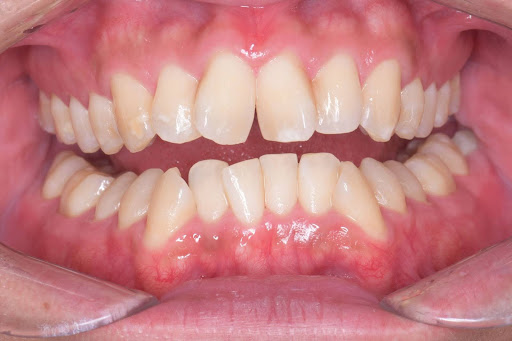

【症例写真】

ガタつきのある歯並びも、マウスピース矯正でここまできれいに整えることが可能です。

<After>